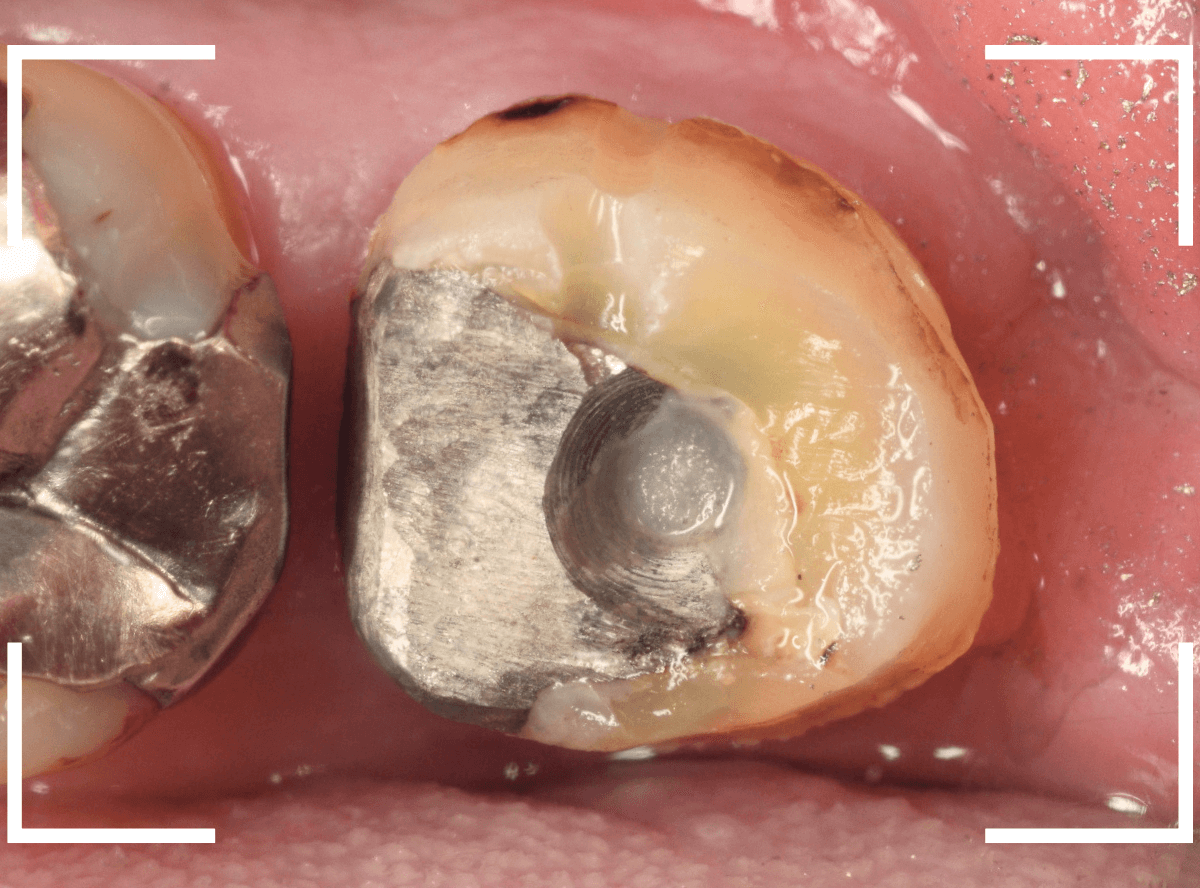

まずは、奥のメタル・クラウンを外します。

メタル・コアが入っていますが、こちらも慎重に外して、中を調べていきます。

レントゲン写真では問題なさそうでしたが、メタルコアを除去すると、中は真っ黒でした。

このように、コアの中で虫歯が進行している場合もありますので、さし歯をやり直す際は、出来る限りコアも外して調べるようにしています。